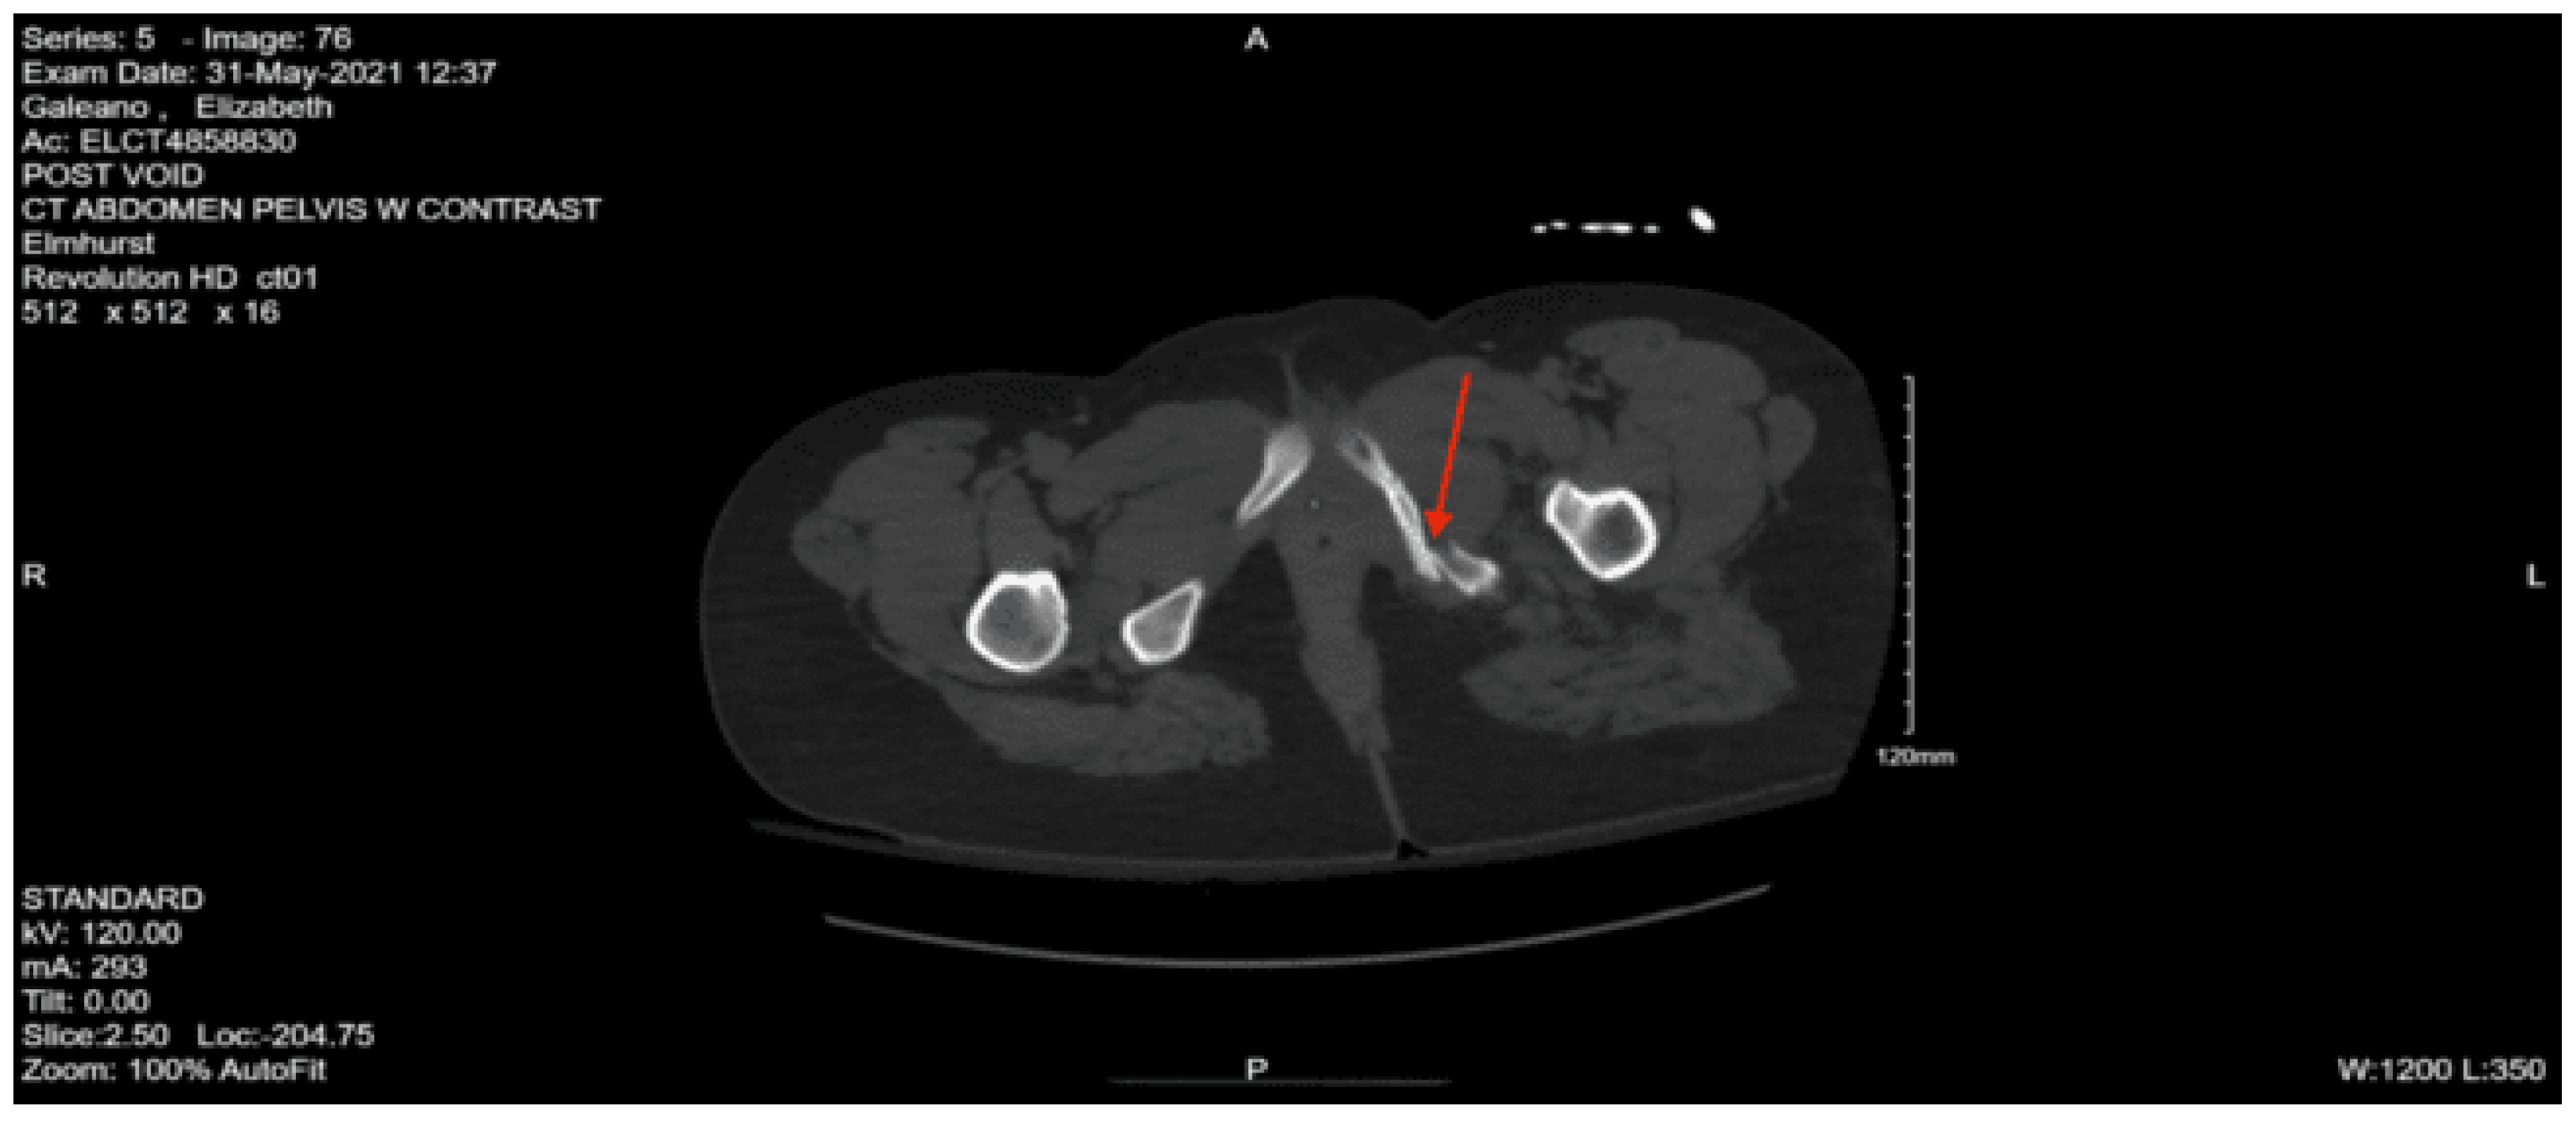

CT angiography abdomen and pelvis with runoff: No visualized arterial blush or pooling of contrast on delayed phase to suggest active arterial bleed. The distal portion of the sacrum is fractured and displaced anteriorly. There is a comminuted fracture through the right iliac bone with moderate displacement. There is a moderately displaced fracture through the right inferior pubic ramus. There are mildly displaced fractures of the right anterior and posterior acetabulum. The anterior fracture appears to involve the articular surface. There is a hemorrhage surrounding the right iliac fracture and a small volume hemorrhage in the right pelvic sidewall and the presacral space. There is a small volume of hemorrhage surrounding the urinary bladder.

A right femoral traction pin was placed by an orthopedic surgeon in the ED. Neurosurgery was consulted for the patient’s multiple spinal fractures and decided to bring the patient to the OR for L1-L5 posterior fusion, L2-3 laminectomy, and L3 corpectomy and cage. A chest tube was also placed on the left in the OR for the pneumothorax. She remained intubated and was admitted to the SICU with post-op instructions of lying flat for 24 hours. Repat CT head showed an expansion of the subdural hematoma, and neurosurgery recommended Keppra for seizure prophylaxis and repeat CT head. The next day, the patient was successfully extubated, and upon further questioning, admitted to trying to hurt herself by jumping out of the window, she was placed on 1:1 monitoring as recommended by psychiatry. Upon reevaluation by orthopedic surgery, they recommended going to the OR after the patient had been medically stabilized. On hospital day 3, the patient underwent flexible sigmoidoscopy to rule out rectal injury; no injury was found. The next day, her chest tube was successfully removed. The patient was found to have a small pulmonary embolism on chest CT, and an IVC filter was placed by interventional radiology on hospital day 7 in preparation for the orthopedic surgery procedure. Later that day, the patient underwent open reduction internal fixation of the right acetabular anterior column and ilium with post-op recommendations of bed rest. Since admission, the patient remained unable to move both lower extremities, though she did gradually regain sensation. She was also unable to void and required intermittent straight catheterization. On hospital day 12, she was evaluated by physical medicine and rehabilitation, who recommended starting bedside physical and occupational therapy, out-of-bed to chair with lift assistance, and discharge to spinal cord injury inpatient rehab if the lower extremity weakness persists. She was transferred to the surgical stepdown unit on hospital day 14. Over her remaining hospital course, the patient regained some ability to move both lower extremities. On hospital day 33, she was discharged to spinal cord injury inpatient rehab.